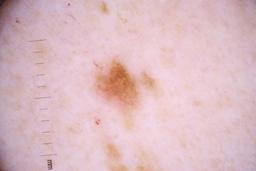

ISIC_4077341

Public

Information

- Created

- Dimensions

- 5184 x 3456

- Attribute to

- The University of Queensland Diamantina Institute, The University of Queensland, Dermatology Research Centre

- License

- CC-BY

- Used in

- Challenge 2020: Training

- Belongs to

- IP_1969685 IL_9238622

Clinical

| Field | Value |

|---|---|

| acquisition_day | 1 |

| age_approx | 50 |

| anatom_site_1 | Trunk |

| anatom_site_2 | Anterior trunk |

| concomitant_biopsy | False |

| dermoscopic_type | contact non-polarized |

| diagnosis_1 | Benign |

| diagnosis_confirm_type | serial imaging showing no change |

| family_hx_mm | False |

| image_type | dermoscopic |

| lesion_id | IL_9238622 |

| patient_id | IP_1969685 |

| personal_hx_mm | True |

| sex | male |

Columns

Showing first 50 images.